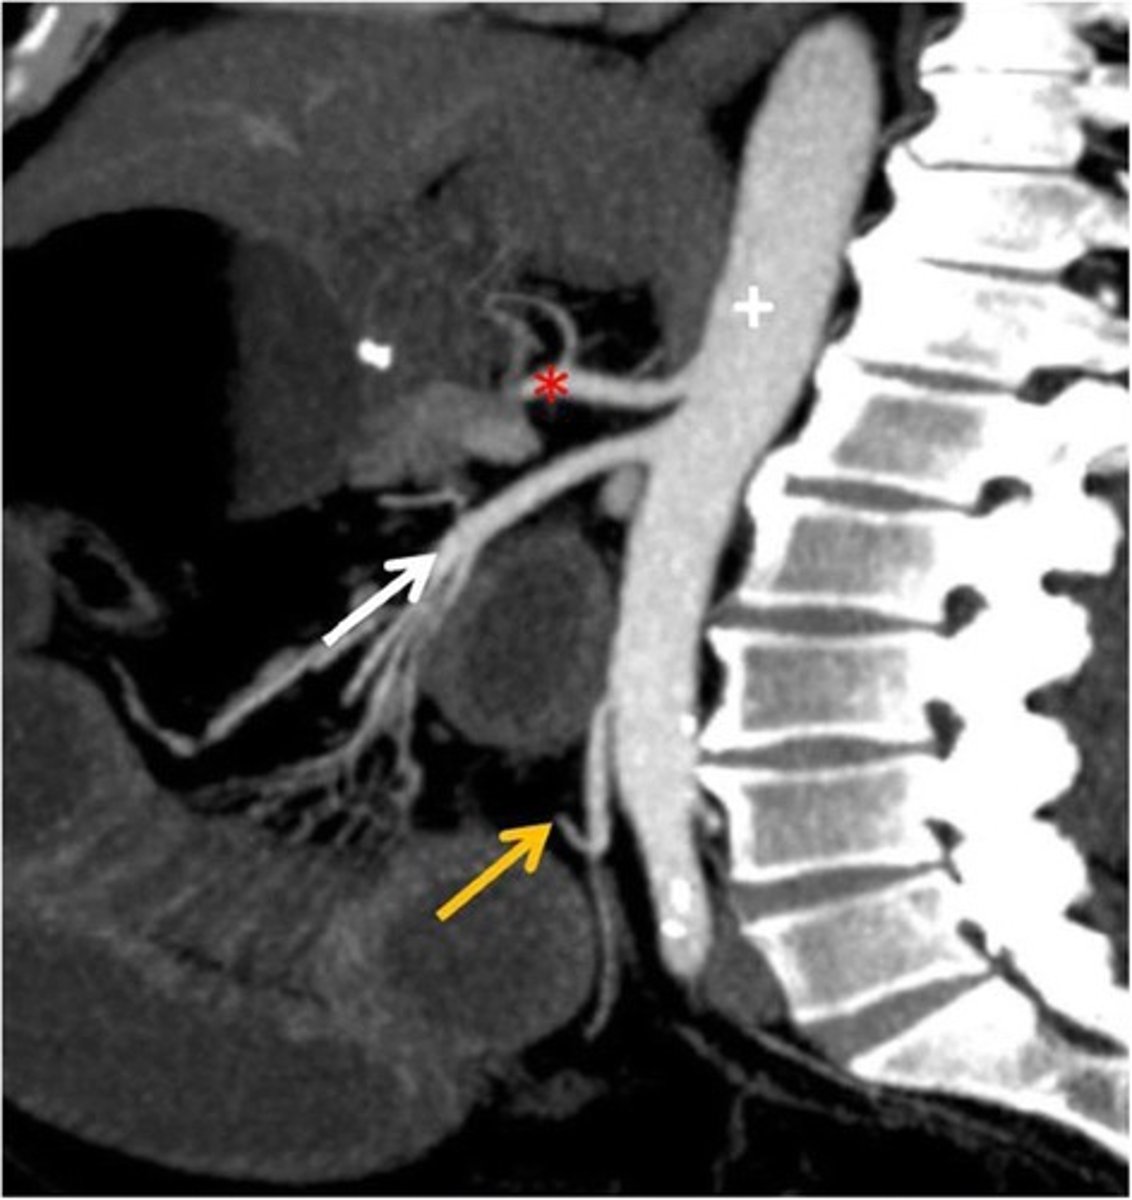

CT Sagittal

What type of image is this

Celiac trunk

What is the red star artery

superior mesenteric artery: midgut

What is the white arrow artery

Inferior mesenteric artery; hindgut

What is the yellow arrow artery